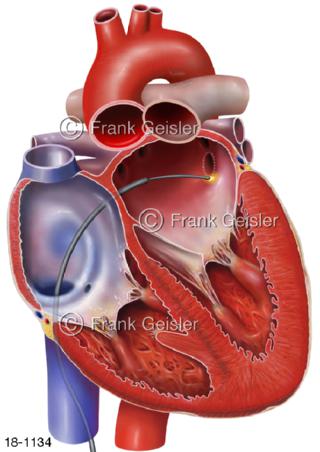

18-1134 Vorhofflimmern, Katheterablation Verödung